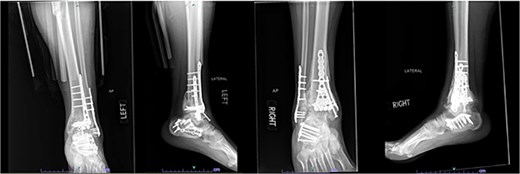

Despite the patient’s noncompliance, he went on to heal uneventfully for the next 2 years until the patient fell from a height of 15 feet, resulting in a left bicondylar tibial plateau fracture and fracture of the left tibial shaft. These injuries required ORIF of his left tibia. Despite the new injury, the hardware from the pilon fractures was in proper alignment (Fig. 4).

Two-year follow-up AP and lateral radiographs of both ankles in patient 2 showing maintained alignment and hardware position.